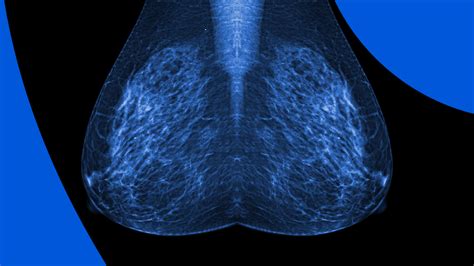

Understanding Mammograms

A mammogram is an X-ray image of the breast used to detect breast cancer in its early stages. It is a crucial tool in preventive healthcare, especially for women over the age of 40. However, the process can be slightly different for women who are breastfeeding.